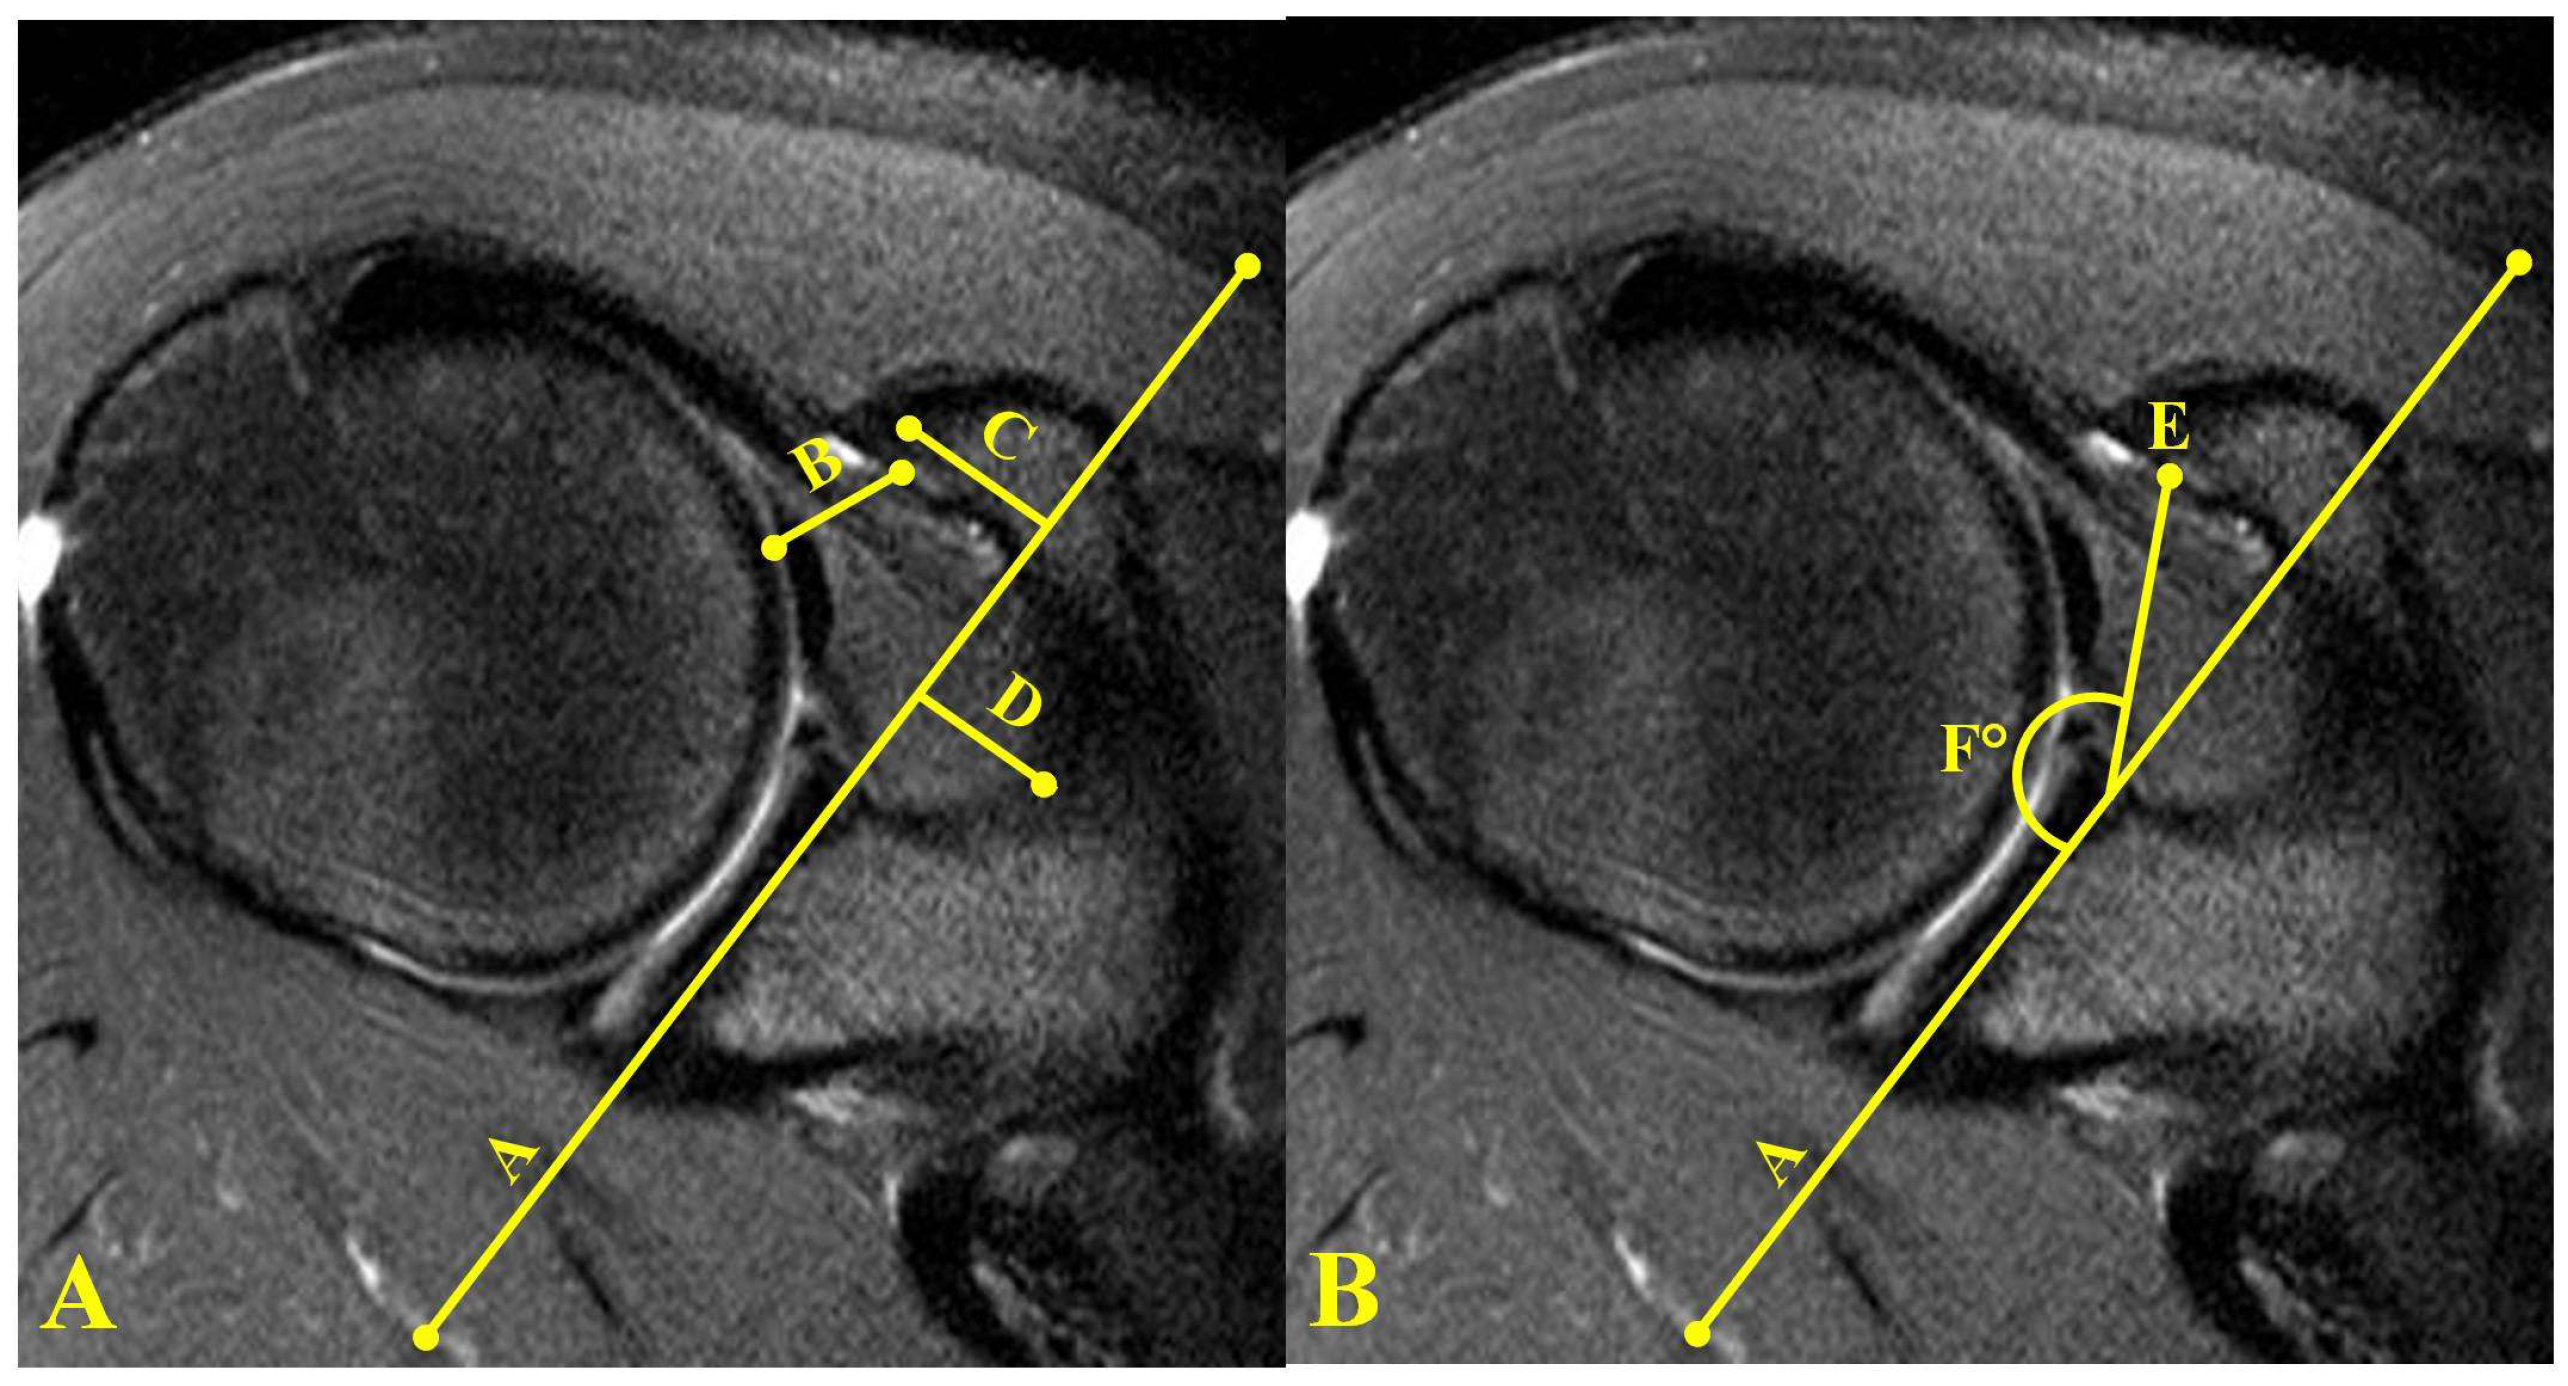

| Axial CR | 6.45 ± 1.72 (3.5–10.5) | 6.42 ± 1.61 (1.8–10.2) | 6.59 ± 1.7 (2.6–11) | 0.920 | 0.668 | 0.577 |

| Axial CO | 12.87 ± 4.91 (2.1–22.1) | 13.15 ± 4.78 (2.7–25.6) | 14.92 ± 4.64 (5.1–24.8) | 0.739 | 0.020 * | 0.035 * |

| Axial CHI | 10.83 ± 3.1 (6.1–20.6) | 10.65 ± 3.33 (4.9–19.4) | 9.14 ± 2.92 (2.8–16.1) | 0.746 | 0.003 * | 0.007 * |

| Axial CGI | 20.04 ± 3.51 (13.2–27.4) | 20.49 ± 3.06 (13.5–28.4) | 21.3 ± 3.18 (15.1–28.7) | 0.425 | 0.042 * | 0.146 |

| CG angle | 146.79 ± 10.3 (127–176) | 146.97 ± 11.52 (121–174) | 143.14 ± 9.74 (126–167) | 0.925 | 0.048 * | 0.046 * |

| Sag CHI | 11.173 ± 3.25 (5.9–24.4) | 10.9 ± 3.31 (4.1–19.6) | 9.47 ± 2.63 (2.6–16.1) | 0.625 | 0.002 * | 0.009 * |